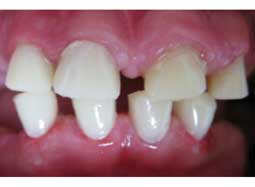

EXAMEN CLINIQUE : (Fig 1, 2, 3)

La patiente présentait une hygiène insuffisante avec accumulation de plaque et une gingivite généralisée. L’examen dentaire a montré un retard d’éruption des canines, des prémolaires et des deuxièmes molaires. Les dents sur arcade présentaient un émail mince, coloré, hypoplasique avec des fractures ; déficitaire en quantité mais correctement minéralisé, dur et brillant et exposition de la dentine par endroits. La 16 et la 26 présentaient des lésions carieuses étendues.

L’examen de l’occlusion a montré des couronnes cliniques courtes avec perte de la dimension verticale.

Le frein médian supérieur était bas situé.